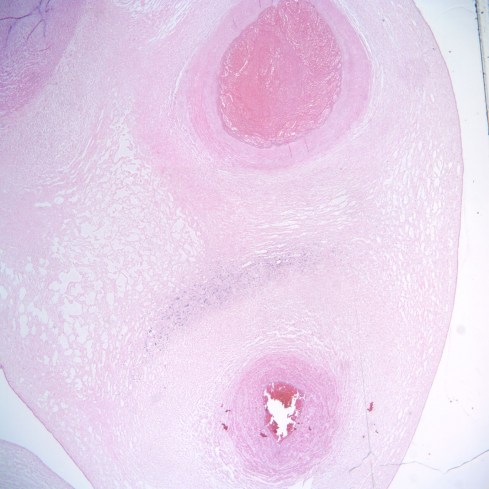

Fig 2a: This is a cross section of the umbilical vein showing a partially occlusive thrombus (marked). This stillborn infant had otherwise unexplained fetal hydrops. (H&E 4x)

Fig 2b: A higher power magnification of the thrombus showing subtle lamination of fibrin in the thrombus.